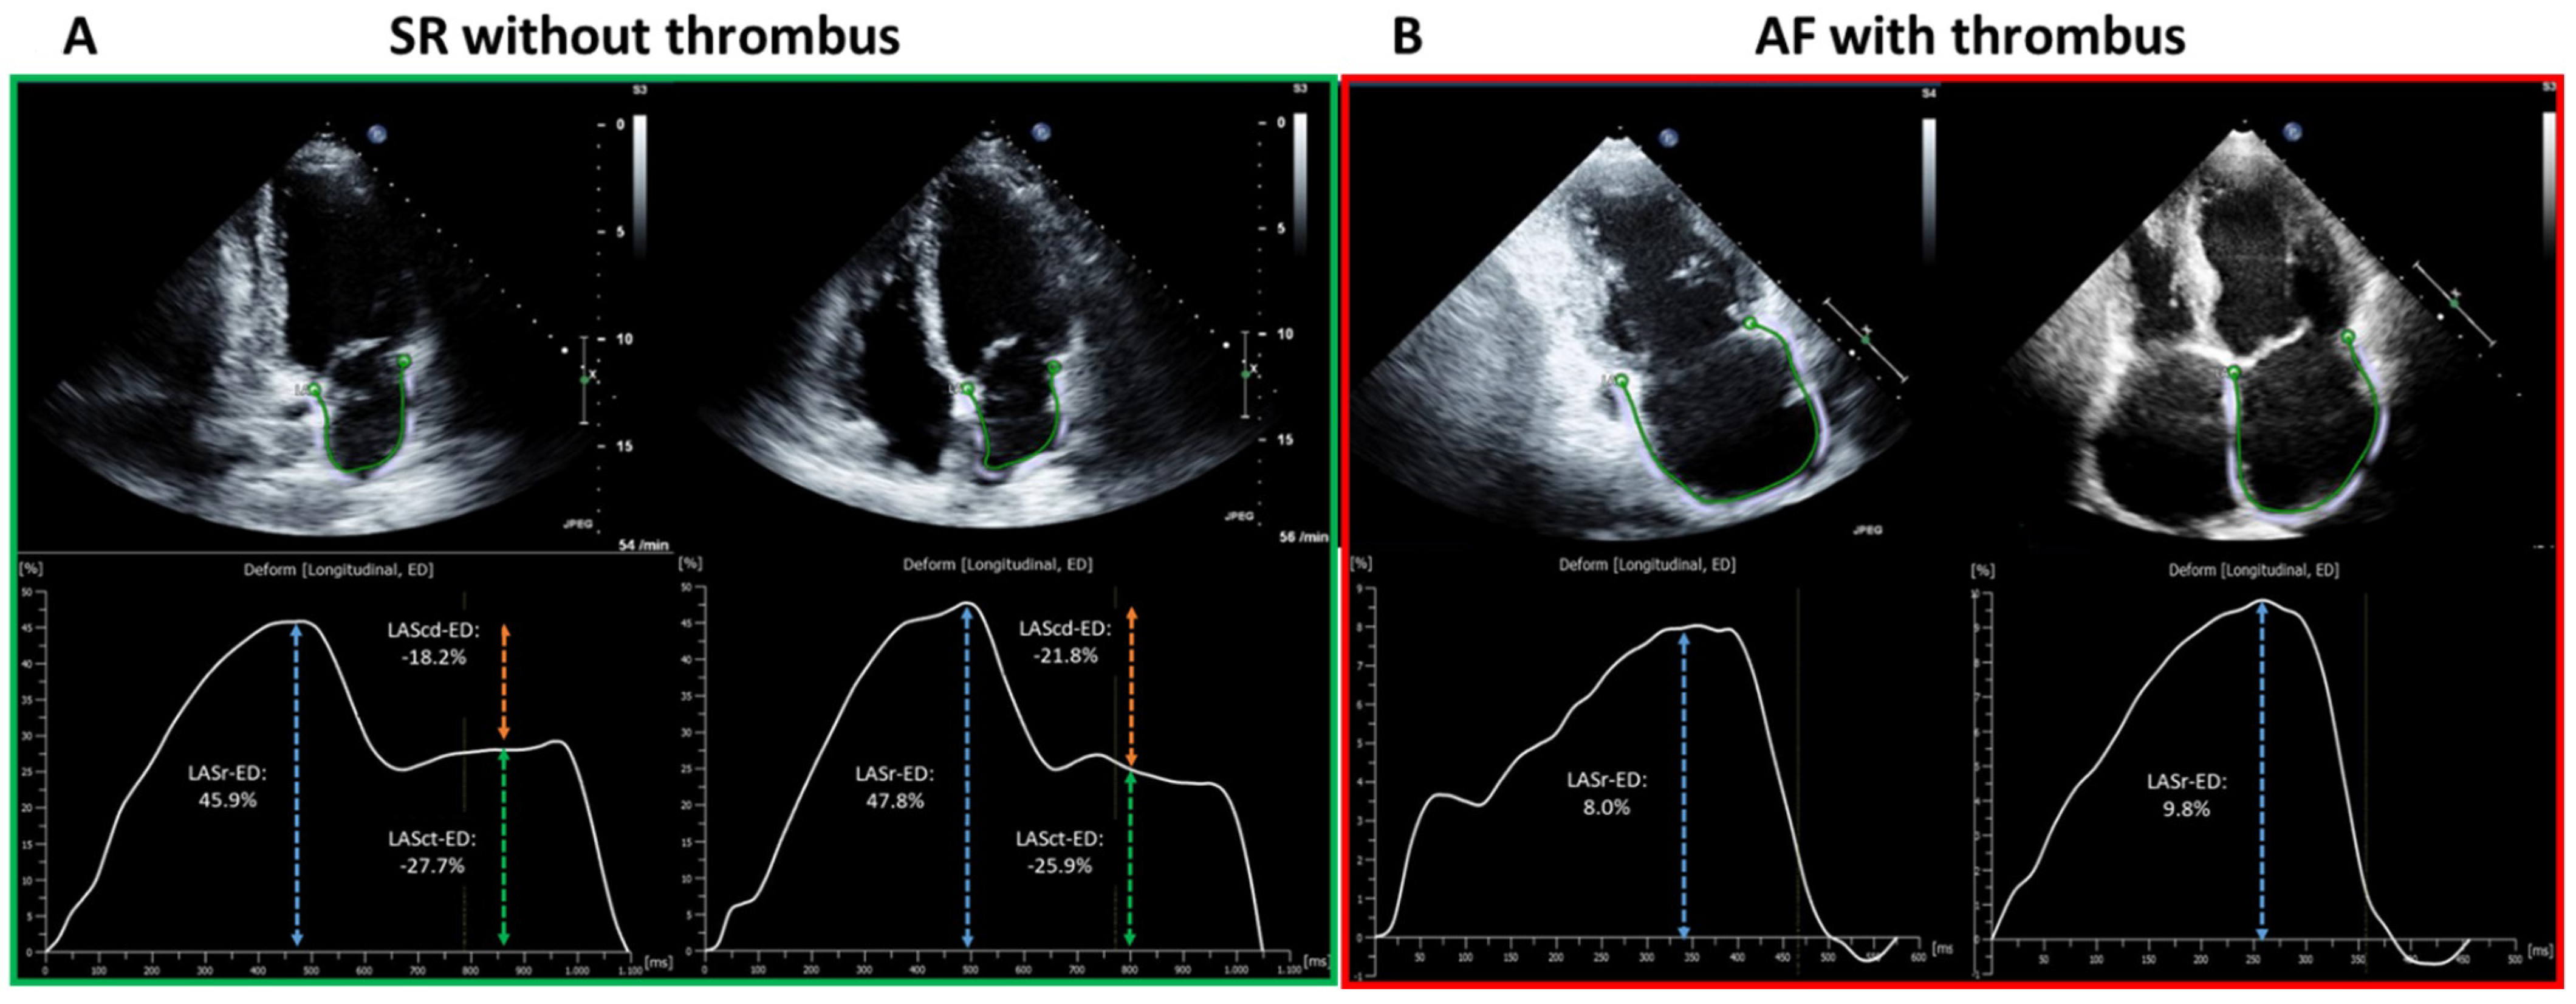

4.2. Left Atrial Appendage Thrombus Is Associated with Impaired Mechanical Function

5.2. General and Rhythm-Specific LA-GLS Thresholds for Left-Atrial Appendage Thrombus